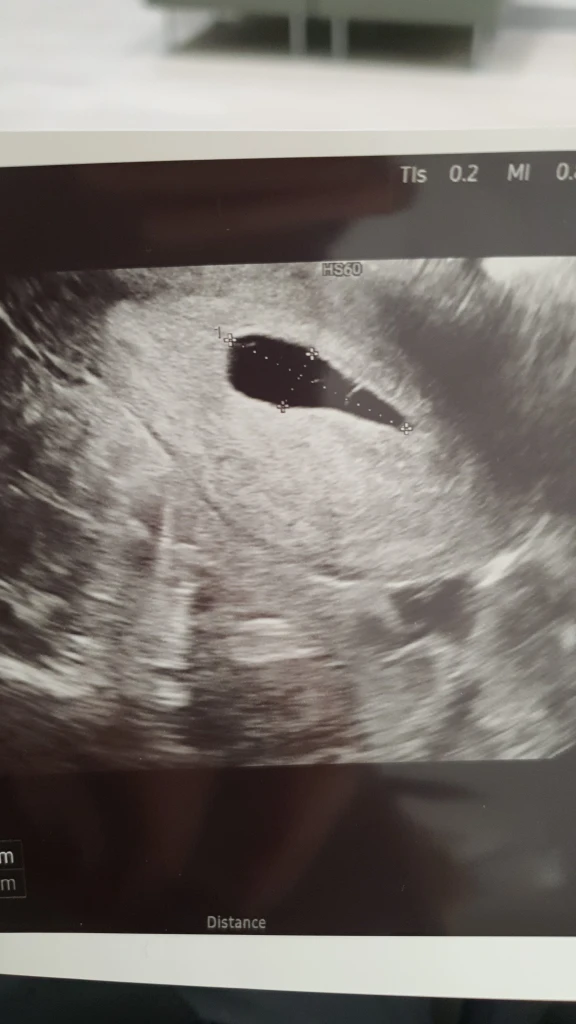

Noh illalla vessassa käydessä asia oli sitten selvä. Vuotoa tuli niin paljon, ettei itselle ollut enää kysymysmerkkejä. Mies ei vieläkään uskonut vaan rauhoitteli, ettei nyt vielä voi olla varma. Mutta mä itkin. Tiesin. Nukuttiin yön yli ja aamulla takaisin päivystykeen, joka laittoi lähetteen Tayssiin. Tayssissa ultrattiin ja todettiin tuulimunaksi. Olin siis raskaana, ilman vauvaa. Ultrassa näkyi vain tyhjä ruskuaispussi.